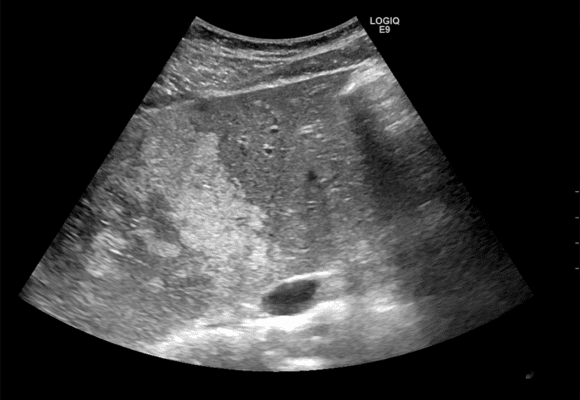

Το λιπώδες ήπαρ (ήπαρ με λιπώδη διήθηση) είναι μια πάθηση κατά την οποία συσσωρεύεται υπερβολικό λίπος στα ηπατικά κύτταρα.

Αν και αρχικά μπορεί να μην προκαλεί συμπτώματα, με την πάροδο του χρόνου μπορεί να οδηγήσει σε σοβαρά προβλήματα υγείας, όπως φλεγμονή, ουλοποίηση και σε προχωρημένα στάδια κίρρωση.